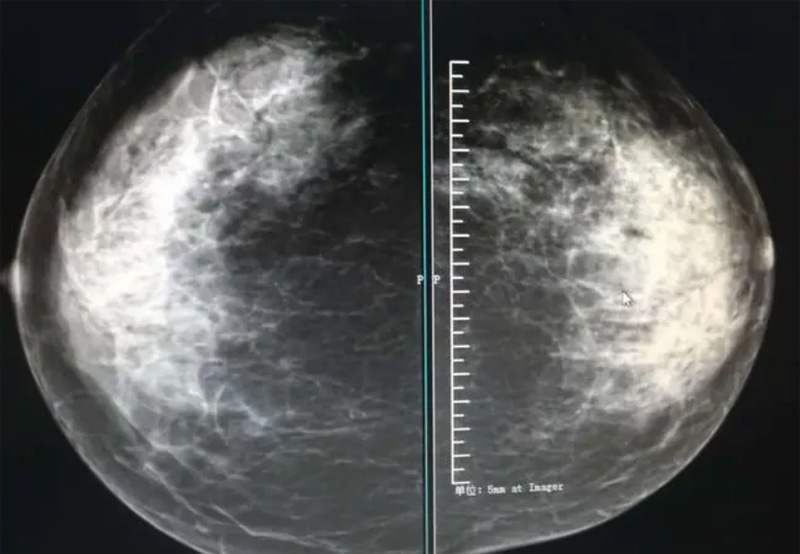

乳腺DR摄影体位有头尾位及内外侧斜位,

乳房在片子的中央,乳头切线位,可见小部分胸大肌,内侧乳腺组织应全部包括在片中,外侧乳腺组织尽可能包括在片中。一张好的MLO位图像显示如下:乳房被推向前上,乳腺实质充分展开,胸大肌可见,较松弛,下缘达到乳头水平,乳头在切线位,部分腹壁包括在片中,但与下部乳腺分开,绝大部分乳腺实质显示在片中。乳腺组织外缘可见乳头的轮廓;乳腺后方的脂肪组织被很好地显示出来,乳房无皱褶。对于CC位及MLO位显示不良或未包全的乳腺实质,可以根据病灶位置的不同选择以下体位:外内侧位(LM)、内外侧位(ML)、内侧头尾轴位(MCC)、外侧头尾轴位(LCC),尾叶位(CLEO)及乳沟位。在临床实践中,对于常规体位上发现的异常改变,可以进一步采取一些特殊的摄影技术,包括局部加压摄影、放大摄影或局部加压放大摄影技术。

2、规范观图程序:屏幕软阅读或在专用日光观片灯下胶片阅读,后者应同时准备白炽强光灯及观片放大镜。注意双侧乳腺配对观察,推荐双眼横向扫描,进行双乳相同部位图像比较分析。

3、乳腺实质背景的确定:观察乳腺实质与脂肪的构成比例,了解乳腺实质类型,以判断对某些乳腺摄影征象敏感性的影响,有利于确定乳腺摄影对疾病的诊断价值。

必须指出的是,美国放射学会提出的乳腺影像报告和数据系统(Breast Imaging Reporting and Data System, BI-RADS)将乳腺分为4型:脂肪型(乳腺内几乎全部为脂肪组织,腺体组织占25%以下)、少量腺体型(乳腺内散在腺体组织,大约占25%~50%)、多量腺体型(乳腺呈不均匀致密表现,腺体组织大约占51%~75%)、致密型(乳腺组织非常致密,腺体组织占75%以上)。这种分型的主要意义在于说明X线对不同乳腺类型中病变检出的敏感性不同,对发生在脂肪型乳腺中病变的检出率很高,而对发生在致密型乳腺中病变的检出率则有所降低,临床医师了解这一点很重要。